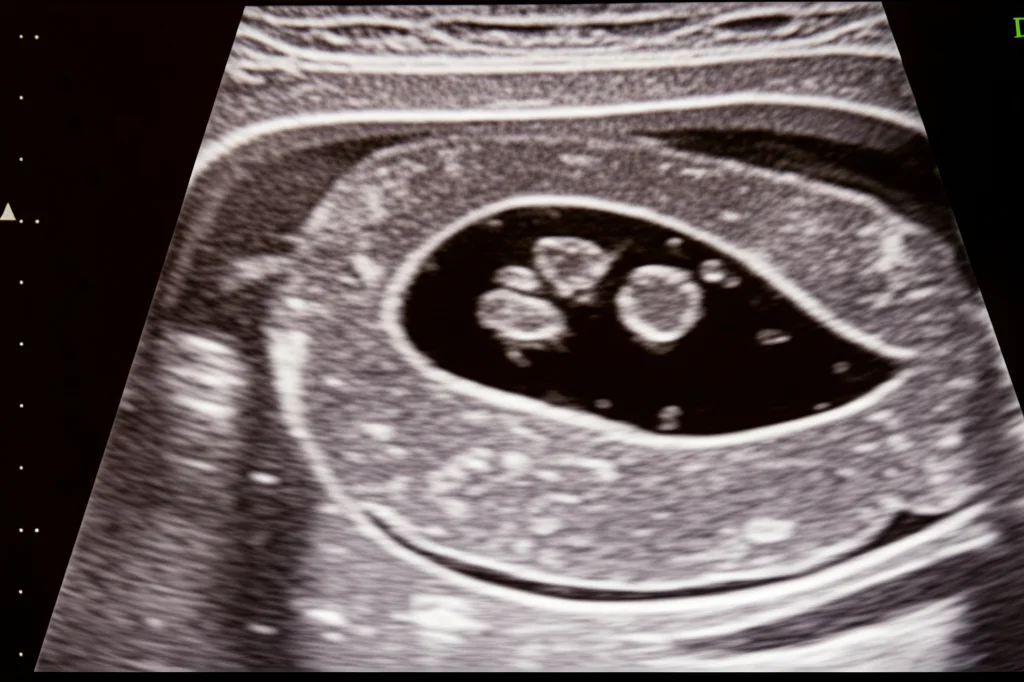

Il Ruolo Chiave dell’Ecografia Prenatale

Qui entra in gioco la magia della tecnologia. L’ecografia prenatale è lo strumento principe per diagnosticare un TSC. Permette ai medici di “vedere” il tumore, valutarne le dimensioni, la morfologia (se è prevalentemente cistico, cioè pieno di liquido, o solido) e la vascolarizzazione (quanto sangue riceve).

Perché questi dettagli sono così cruciali? Perché ci danno indizi fondamentali sulla prognosi. Studi recenti, inclusa un’analisi retrospettiva condotta su 16 casi presso l’Ospedale Universitario di Brno tra il 2005 e il 2020 (di cui vi parlerò tra poco), hanno evidenziato alcuni marker ecografici importanti:

- Prognosi più favorevole: Tumori prevalentemente cistici. Questi sono spesso benigni e associati a minori complicanze.

- Prognosi più riservata: Tumori prevalentemente solidi, a crescita rapida e molto vascolarizzati. Questi possono “rubare” sangue al feto, creando uno shunt artero-venoso. Questo sovraccarica il cuoricino del piccolo, portando potenzialmente ad anemia fetale, idrope (accumulo di liquidi), ingrossamento del cuore (cardiomegalia) e della placenta (placentomegalia), fino all’insufficienza cardiaca.

L’ecografia monitora anche la quantità di liquido amniotico (troppo, detto polidramnios, o troppo poco, oligoidramnios, possono essere segnali d’allarme) e la crescita generale del feto.